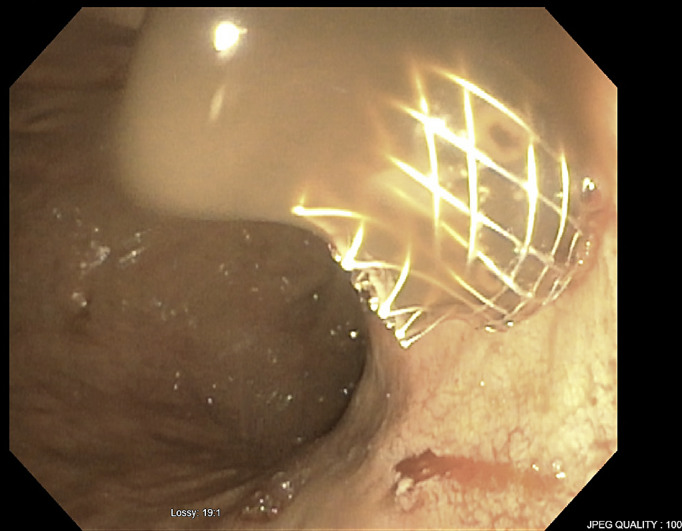

Case presentation: Three patients, average age 75 years (two men, one woman), underwent EUS-guided drainage using LAMS for an infected liver cyst, infected liver hematoma within a hepatocellular carcinoma lesion, and a symptomatic simple liver cyst, respectively. All the hepatic fluid collections were in the left hepatic lobe and had an average diameter of 11 centimeters (cm). Only the female patient with a symptomatic cyst had prior percutaneous drainage. Successful LAMS placement was achieved in all cases. Clinical success, defined as cyst resolution or significant size reduction, was observed in all patients. The superinfected liver cyst showed complete resolution, yet the stent remained in place as the patient transitioned to hospice and subsequently passed away. In the case of the superinfected liver hematoma, the stent was removed after 2 months. No recurrence was observed in follow-up imaging 8 months later, and the patient passed away. The symptomatic simple liver cyst patient had the stent removed 15 months later, with no recurrence in imaging 11 months of post-stent removal.

Conclusion: EUS-guided LAMS placement emerges as a less invasive and viable option for treating symptomatic and/or infected hepatic fluid collections compared to surgery or percutaneous drainage. While it may be a preferable choice in institutions with the requisite expertise, further studies are essential to establish its definitive role as a first-line intervention.